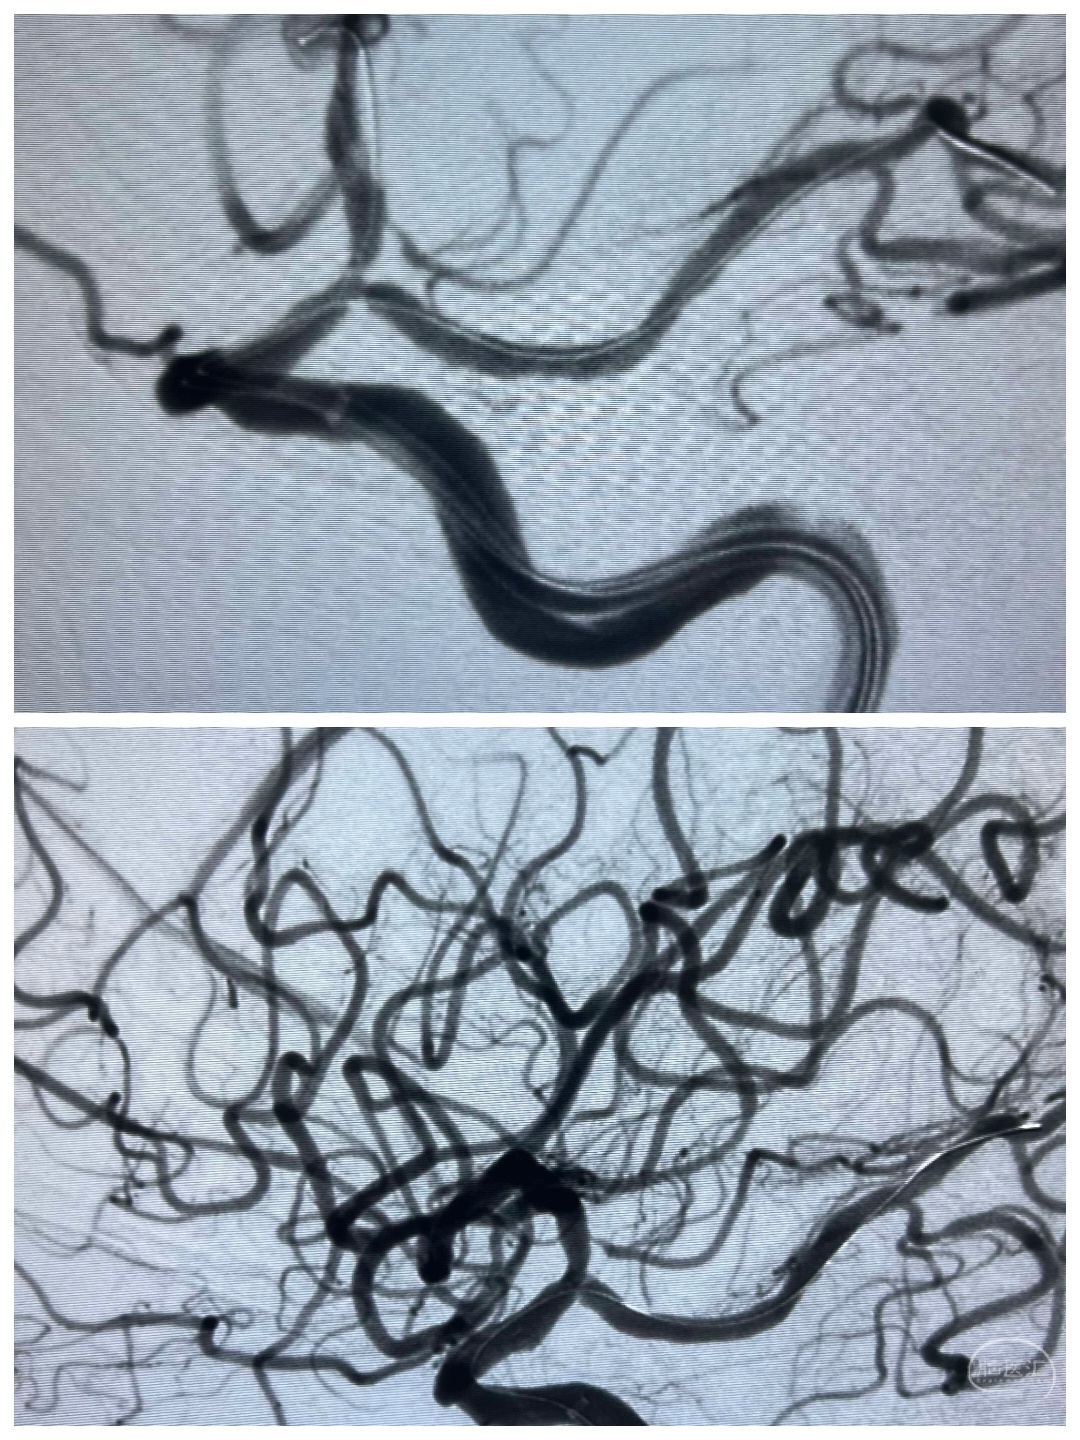

病例五 、左侧颈内动脉末端狭窄

刘某,女性,69岁,因“视物模糊伴头晕不适一个月”入院。

MRI提示左枕叶脑梗塞,粗看MRA还可以,左侧血管较右侧血管稍稀疏纤细一点。

进一步DSA检查提示左侧颈内动脉末端狭窄~果然比MRA精准

予以双导丝双球囊扩张,稀疏的颅内血管终于开枝散叶。术后患者症状改善,治疗效果非常满意。